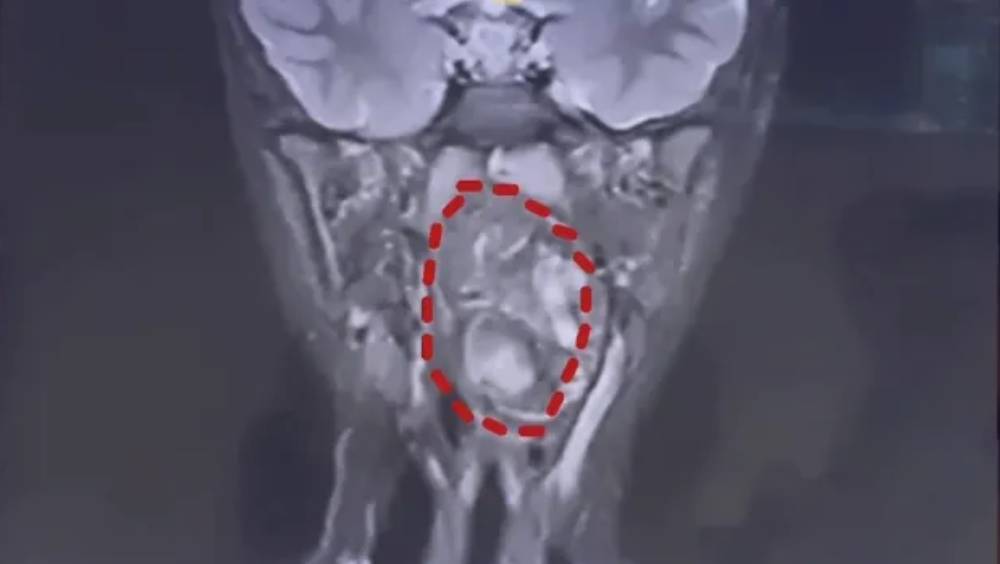

鼻鼾聲震天揭駭人真相 6歲童喉藏「雙胞胎」畸胎瘤